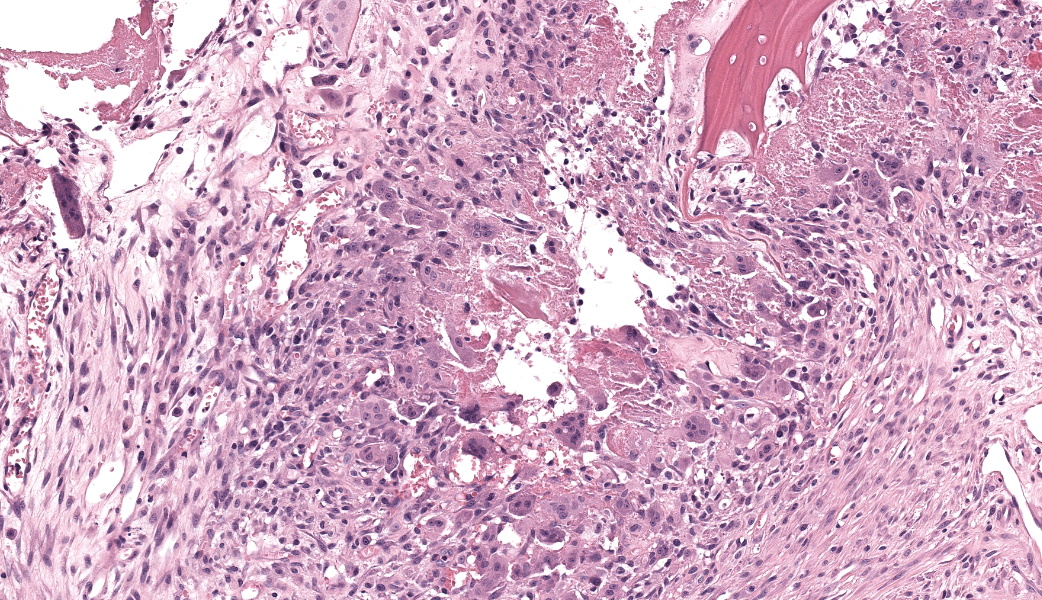

Expanding the anterior uvea, effacing the iris, and markedly expanding the suprachoroidal space is a densely cellular, unencapsulated neoplasm of neuroepithelial cells. Neoplastic cells are arranged in variably dense sheets and as palisading columnar cells surrounding a central lumen (Flexner-Wintersteiner rosettes) or surrounding eosinophilic fibrillar material (Homer-Wright rosettes) surrounded by collagenous and occasionally myxomatous stroma. Neoplastic cells are polygonal to fusiform, have a high nuclear to cytoplasmic ratio, and have distinct cell borders. The nuclei are round to ovoid, finely stippled, and have indistinct nucleoli. There are 16 mitoses in 10 high power fields and anisokaryosis is mild. The neoplastic cells are impinging upon the optic nerve, which has multifocal axonal degeneration and is infiltrated by a population of histiocytes, lymphocytes, and plasma cells, as well as scattered foci of hemorrhage. The retina has multifocal, disorderly components of viable photoreceptor and retinal ganglion cells, dense necrosis, glial scarring, and presumed Mueller cells. The retina is diffusely detached and lacks apparent retinal vessels. The retinal pigment epithelial cells have multifocally migrated through to the inner layers of the retina. The cortical lens fibers are moderately liquefied and homogenous and there is posterior migration of the lens epithelium, consistent with cataractous change. The corneal epithelium has marked, segmental ulceration and the outer corneal stroma in this area is mineralized with occasional breaks and is densely compact with fibrosis. Multifocally throughout the corneal stroma are areas of fibrosis, vascularization, and scattered neutrophils.Contributor's Morphologic Diagnoses:

Medulloepitheliomas are classified as benign or malignant. Criteria for malignancy set forth by Zimmerman et al. include poor differentiation, sarcomatous change, increased mitotic rate or nuclear pleomorphism, and invasion into other structures such as the sclera or uveal stroma.1 In most veterinary cases with continued follow-up, malignancy was rare. In all cases, enucleation is the preferred treatment method.